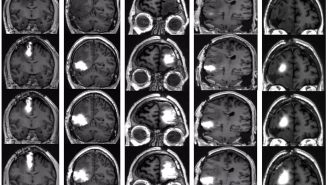

The results: Remarkably, none of the participants experienced serious neurological complications, while MRI scans revealed that the chemo pump had effectively saturated the area around their cancer with the drug.

While the trial was too small to determine whether the treatment could help patients live longer, biopsies of participants’ brains before and after treatment revealed that it significantly decreased the number of actively dividing tumor cells — without affecting their normal brain cells.